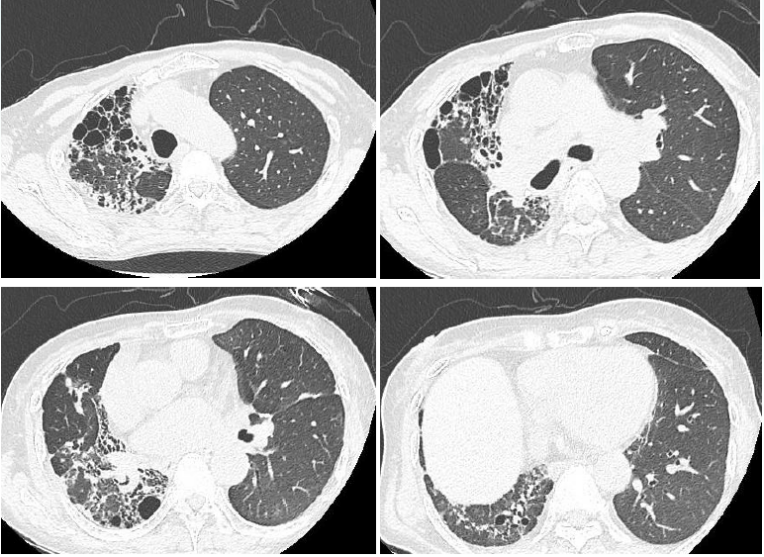

术后第1天:患者无发热,气管镜下示左肺下叶各基底段和背段管腔内少量黄白色黏痰;PCT 0.58 ng/ml(↑),血常规:WBC 12.9×109/L,NEUT% 81.3%,LYM 0.52×109/L。复查胸部CT:左侧移植肺肺野相对清晰,肺外带胸膜下可见少量斑片状磨玻璃(图9)

图片

9  患者左肺移植术后第1天胸部CT(2020-12-31)

术后早期BALF培养提示碳青霉烯类敏感的铜绿假单胞菌,继续哌拉西林他唑巴坦4.5 g q8h ivgtt治疗,加用阿米卡星0.2 g q12h雾化吸入。经治疗,患者无发热、咳嗽、咳痰,可逐步完全脱氧行走。术后第8天,复查胸片示左侧移植肺肺野较前清晰(图10)

10  患者肺移植术后第1天和第8天胸片对比